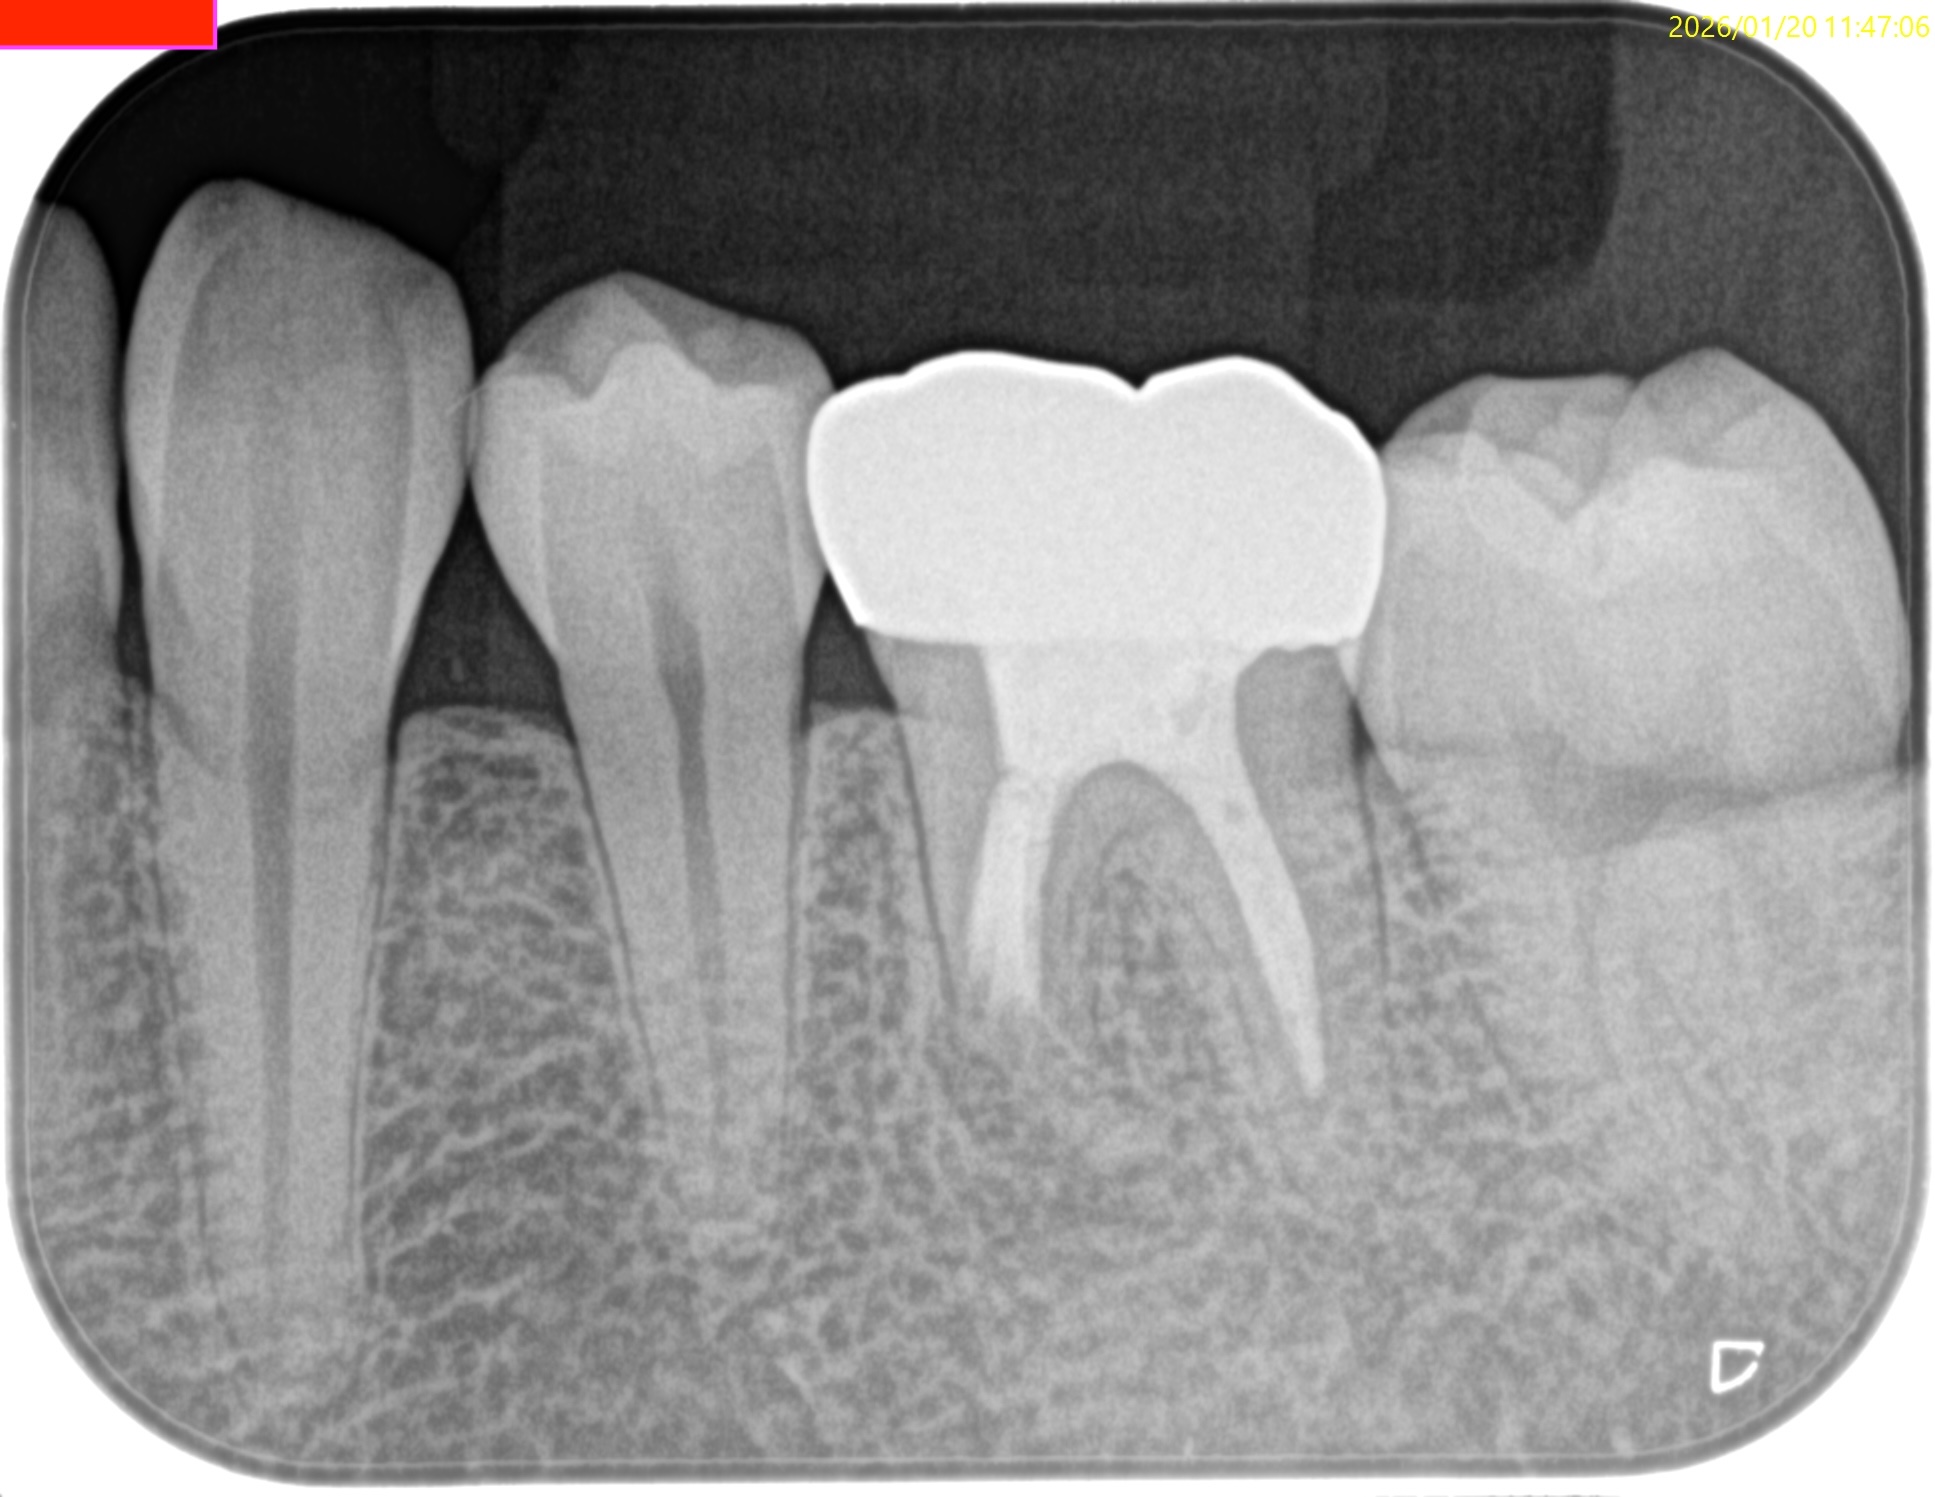

術後にPA, CBCTを撮影した。

問題はないだろう。

Post-op 1yr Endo test(2026.1.20)

術後の骨欠損は完治した。